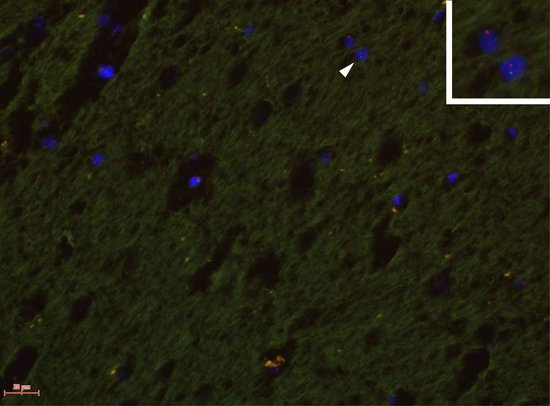

科学家们第一次在一位母亲的大脑中发现胎儿细胞

一位母亲或许一直都把她的孩子放在心里。研究人员称,最新研究结果发现胎儿的细胞能够移动到他们母亲的大脑中。科学家补充道,尚不确定的是这些细胞是否对母亲有益或者有害,又或者两者兼有。